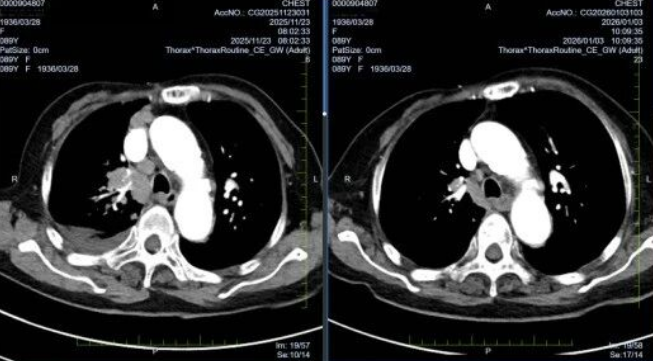

基因检测报告回报后,患者开始口服靶向药物。服药1月余复查胸部CT显示:右肺原发灶缩小约20%,纵隔淋巴结明显退缩;头颅增强MRI示脑转移灶缩小近50%,水肿带显著吸收。治疗期间过程顺利,无明显不良反应。目前患者病情稳定,已恢复部分自理状态,定期门诊随访。